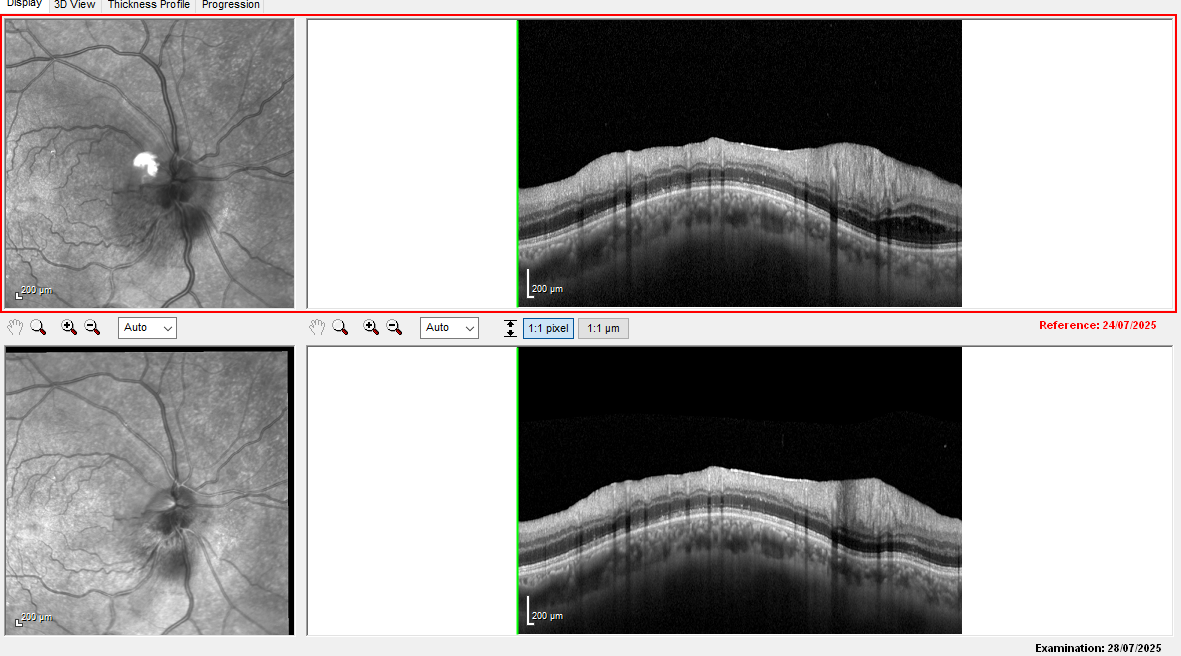

The loss of GCL is unfortunately not good.

The attached OCT compares 24 (worse) and 28 July (slightly better).

• Optic disc edema improving post-IV steroids (see attached images)

Macular OCT: is there seeping of fluid under the macula causing this worsening in vision?